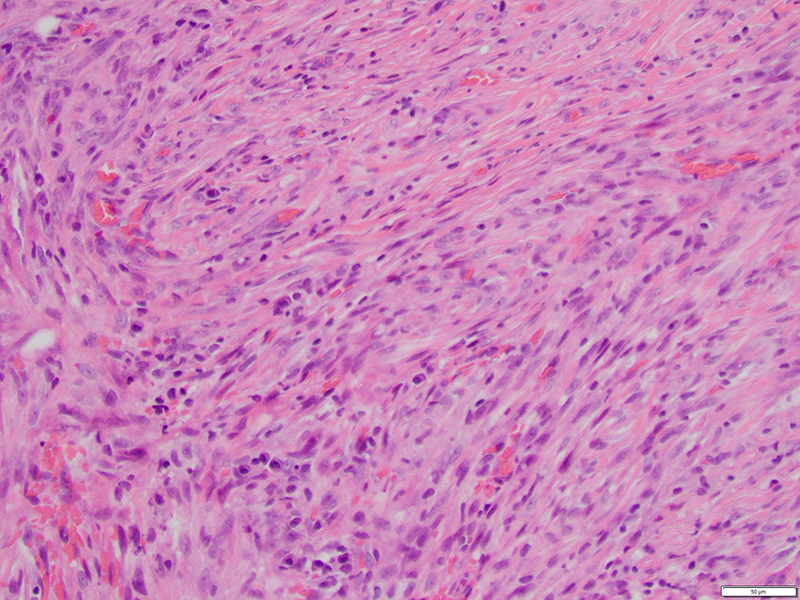

Limited patient history was available for review. The breast lesion consisted of a population of spindle cells with interspersed thick collagen bundles, focal lymphocytic aggregates and some extravasated erythrocytes (Fig 1). No overt cytologic atypia was observed and mitotic figures were infrequent (Fig 2).